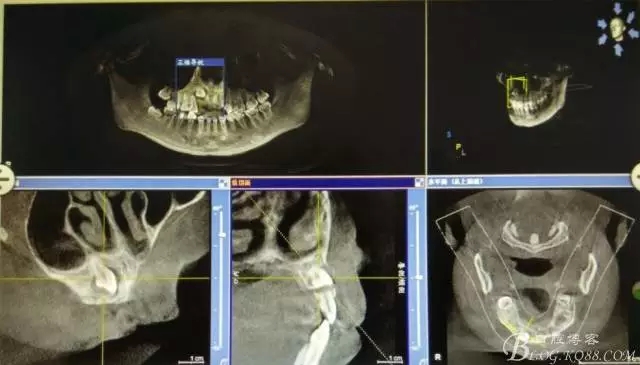

病例資料: 患者、柴xx、女、16歲。專科檢查及病歷如下圖: 患者同意我院正畸科建議,遂轉(zhuǎn)診倒外科。術(shù)前簽知情同意書。 治療過程: 圖1.術(shù)前的CBCT檢查:13阻生,疑為含牙囊腫。縱剖面顯示12牙根吸收至根尖1/3。 圖2.局部麻醉下 。行唇側(cè)弧形切口,12松動不到1°。 圖3.翻瓣、暴露骨面。 圖4.去骨、 暴露13牙冠 圖5.去骨、逐漸顯露13。 圖7.拔除13. 圖8.摘除囊壁 圖9.必須完整剝離囊壁。 圖10.摘除囊壁后形成的骨腔 圖11.超聲骨刀12根尖倒預(yù)備 圖13. 消毒棉球骨腔內(nèi)隔濕血液,紙尖干燥倒預(yù)備好的根管 圖14. 紙尖無血即可 圖15。MTA倒充填 圖16.骨腔填塞膠原蛋白海綿 圖17.拔除的13及摘除的囊壁 圖18.縫合 圖19.術(shù)后x線根尖片影像:MTA封閉根尖